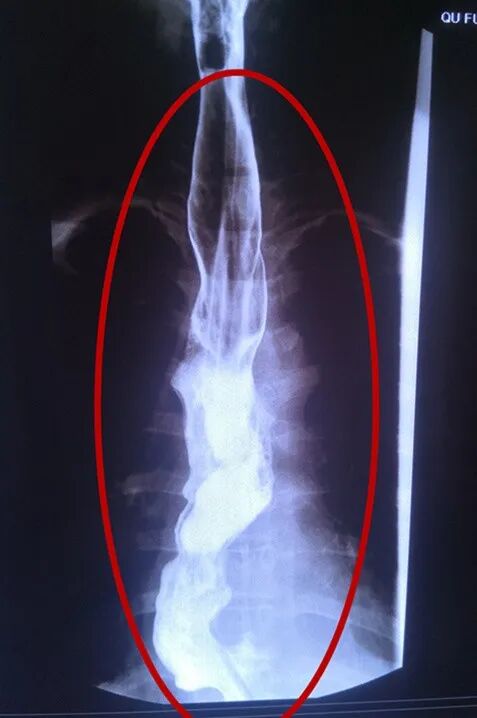

术前全段食管水肿变宽肥厚

向医生连连道谢的李大姐,今年42岁,30年前即出现进食不畅的问题,服药后可减轻,曾在多家医院多次就诊,曾有专家建议其行全食管切除术,但因该手术风险高、创伤大、术后生活质量差,李大姐及其家属难以接受而放弃。近几个月以来,李大姐症状明显加重,进食即吐,遂来到曲阜市中医院胸外科就诊,检查后诊断为贲门失弛缓症。因患者贲门部长期狭窄受压,导致全段食管水肿肥厚变宽,最宽处可达10cm(正常食管很少超过2cm)。长期的进食障碍导致其贫血、低蛋白,体质较差。